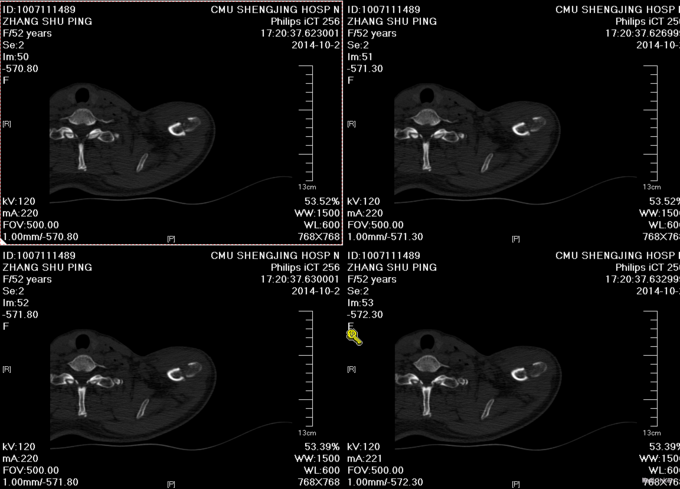

患者入院后完善相关检查,胸部CT报左气胸,请胸外科行闭式引流后,患者血氧约97%。择期行手术治疗。无其他手术禁忌症后行左锁骨骨折切开复位内固定术,术后3天后闭式引流液减少到10ml予以拔除。术后14天后出院。